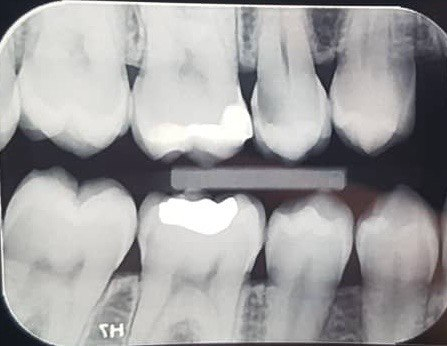

13. what are the radiolucency features in mesial and distal root surface of the tooth # 4.5 respectively?

14. Which surfaces shows recurrent caries?

15. Which surface shows recurrent caries?

16. What are the caries level in mesial and distal surfaces of the tooth # 4.6 respectively?